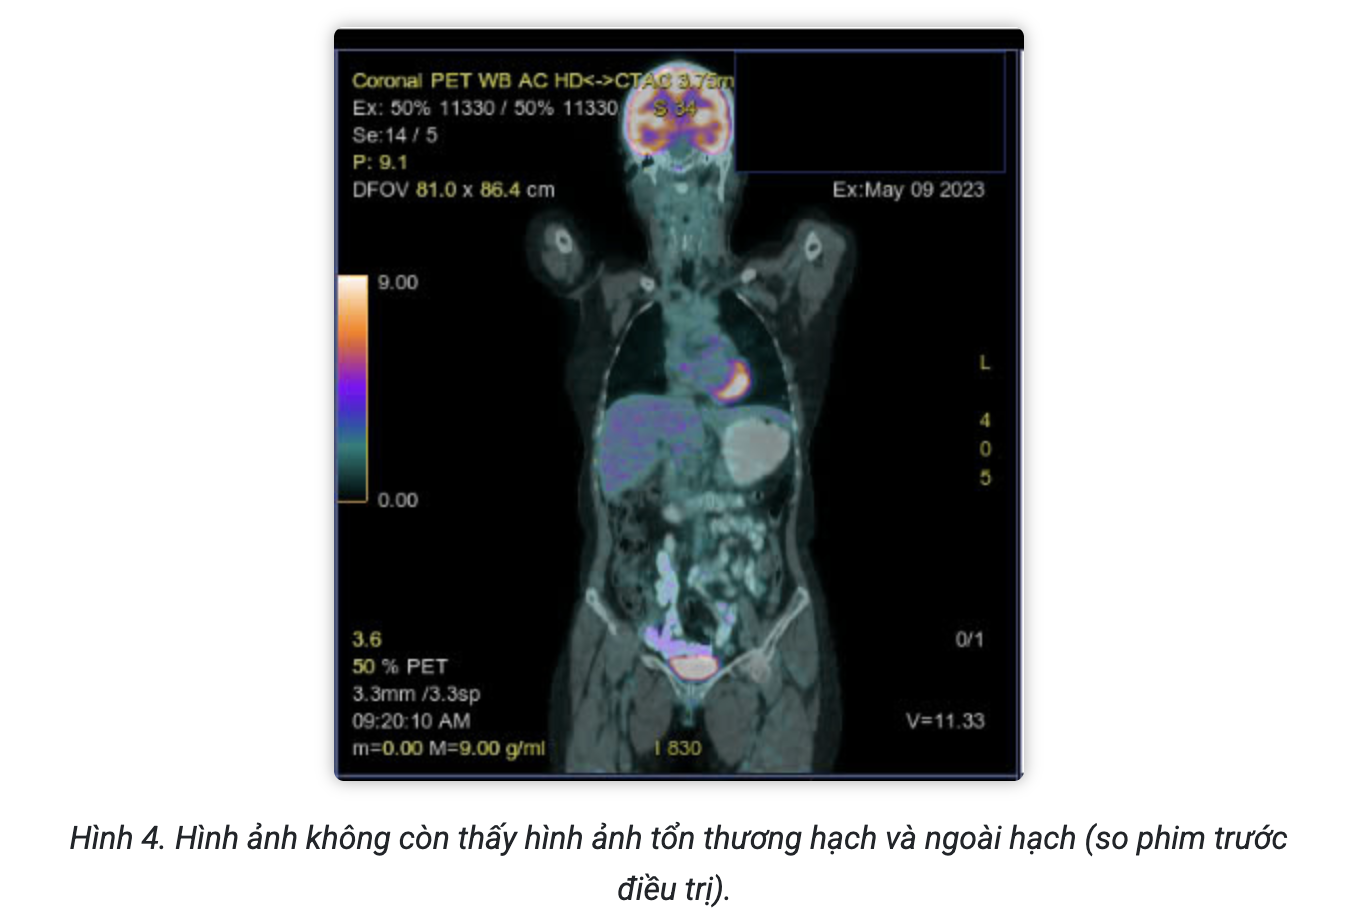

Sau điều trị 4 chu kỳ, bệnh nhân được chụp PET/CT đánh giá đáp ứng điều trị:

Kết luận:

- Không thấy hình ảnh tăng chuyển hóa ở tiểu khung

- Hình ảnh tăng chuyển hóa FDG lan tỏa ở tủy xương đốt sống ngực, thắt lưng, xương chậu 2 bên do phản ứng.

- Hình ảnh vài dải mờ và đám kính mờ phân bố rải rác nhu mô 2 phổi, không tăng chuyển hóa FDG.

Theo thang điểm 5-PS, bệnh nhân có đáp ứng là điểm 1 tại các tổn thương. Bệnh đáp ứng hoàn toàn trên PET/CT.